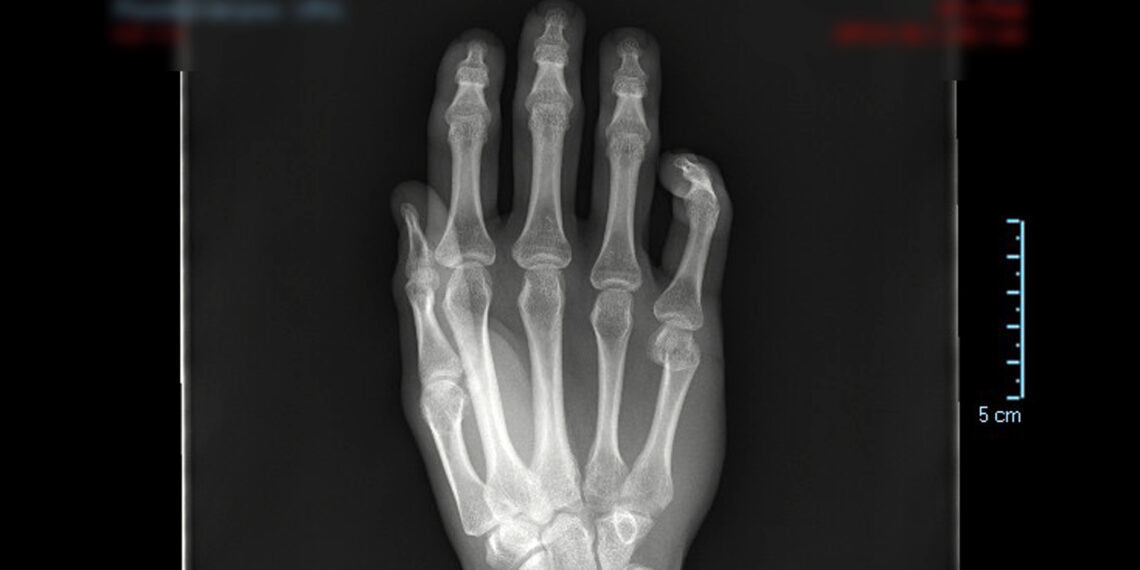

Las patologías más habituales suelen ser fracturas, Luxaciones y subluxaciones, tendinopatías, bursitis, neuropatías… Todas ellas tienen respuesta en el nuevo modelo de atención al paciente especializado en las patologías del Miembro Superior. “Cuando acude por primera vez al médico se activa un modelo de diagnóstico y recuperación planificado personalmente para cada paciente en el que se implican distintos especialistas del centro sanitario (Traumatología, Medicina Física y Rehabilitación Reumatología, Nutrición, Rehabilitación y Fisioterapia)”, explica la fisioterapeuta, Belén Aranda Jimenez. La especialista destaca la labor de coordinación y trabajo transversal de la Unidad del Miembro Superior; “trabajamos de forma coordinada para establecer el mejor abordaje posible y garantizar una recuperación optima”.